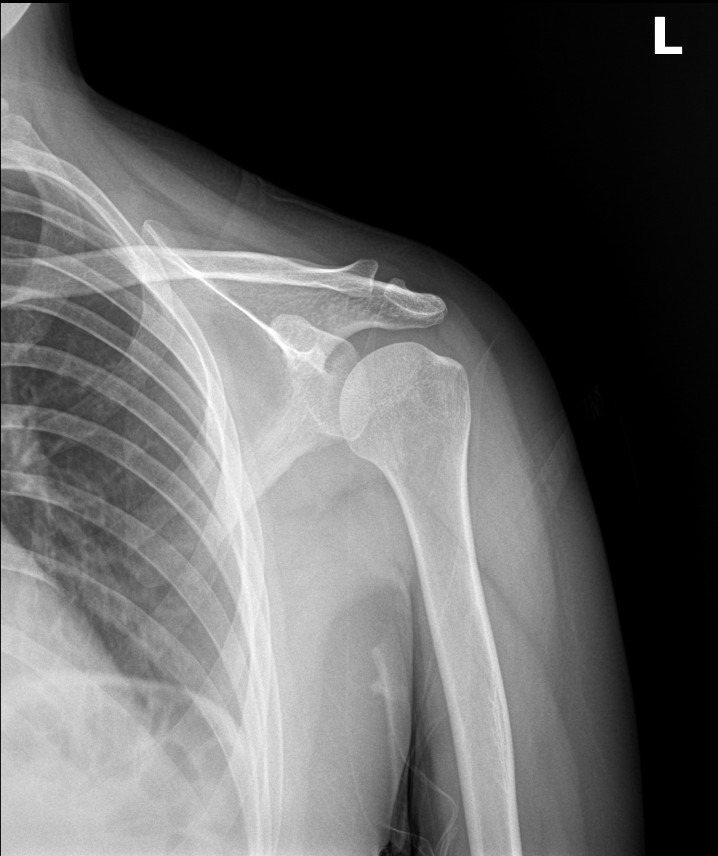

영상 검사를 다시 확인했습니다. 견봉뼈는 정상 범위였습니다.

| 견봉뼈가 자람 | 견봉뼈 정상 |